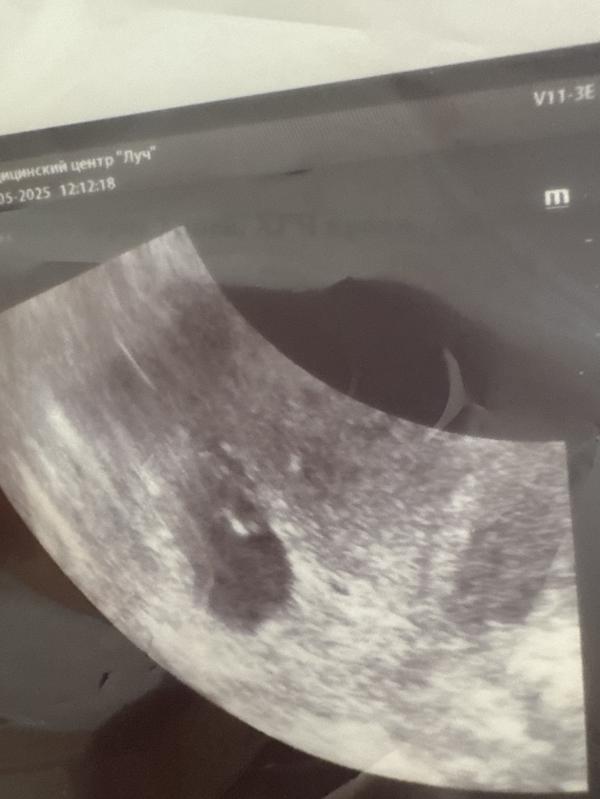

Срок ровно 7 недель. Легла.

Узистка: вижу плодное яйцо, желточный мешочек… эмбрион не вижу. Вот он тут должен быть. Ну не паникуйте такое бывает.

Ищет. Показывает эмбрион с сердечком немножко удалось послушать. Ктр 6,8 мм.

Эмбрион соответствует сроку, если это верные данные 0,68 мм и сердцебиение есть. Но боже … я теперь так боюсь